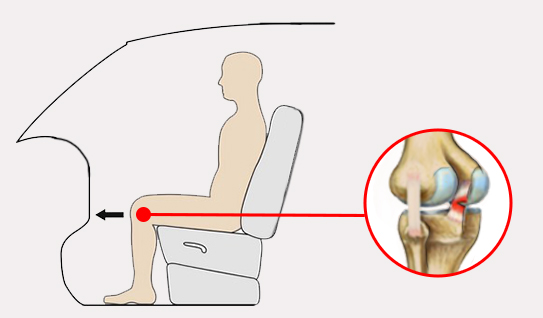

Uraz najczęściej występuje w wyniku wymuszonego tylnego przemieszczenia piszczeli. Do rozerwania PCL jest konieczna duża siła, dlatego bardzo często przyczyną urazu są wypadki samochodowe, gdzie dochodzi do uderzenia kolanem o deskę rozdzielczą.

Uraz najczęściej występuje w wyniku wymuszonego tylnego przemieszczenia piszczeli. Do rozerwania PCL jest konieczna duża siła, dlatego bardzo często przyczyną urazu są wypadki samochodowe, gdzie dochodzi do uderzenia kolanem o deskę rozdzielczą.

Orteza kolana RAPTOR/2RA stabilizuje staw w płaszczyźnie strzałkowej i czołowej. Orteza RAPTOR/2RA posiada 4-punktowy system podparcia, który doskonale stabilizuje i odciąża staw kolanowy. W przypadku uszkodzonego więzadła krzyżowego tylnego (PCL), kość piszczelowa ma tendencję do nadmiernego przemieszczania się w kierunku tylnym względem kości udowej. Konstrukcja przednio-tylna ortezy pozwala na zabezpieczenie piszczeli i ustawienie jej w osi stawu kolanowego.

W przypadku uszkodzonego więzadła krzyżowego tylnego (PCL), kość piszczelowa ma tendencję do nadmiernego przemieszczania się w kierunku tylnym względem kości udowej. Konstrukcja przednio-tylna ortezy pozwala na zabezpieczenie piszczeli i ustawienie jej w osi stawu kolanowego.